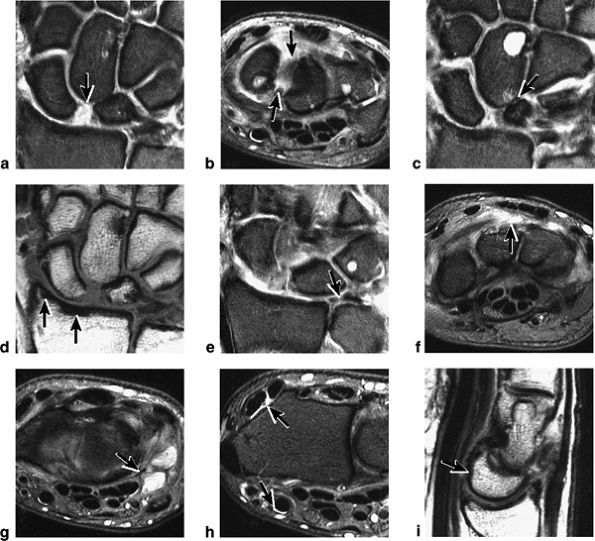

FIGURE 10.31 ● Normal coronal anatomy. (A) Fatty atrophy or denervation of the thenar muscles raises the possibility of median neuritis, and in such cases the median nerve is closely examined for enlargement or increased signal. (B) Tenosynovitis of the flexor tendons with fluid in the tendon sheaths can occasionally cause enough mass effect on the median nerve to cause median neuritis. (C) The first carpometacarpal joint (the articulation between the trapezium and the base of the first metacarpal) is a common location for degenerative arthrosis, often visualized at the corner of a coronal image. (D) Fluid in the pisotriquetral recess is a common finding. In the absence of other findings such as degenerative changes at the joint, a small amount of fluid in the pisotriquetral recess is probably of no significance. (E) Fractures of the distal scaphoid extending to the articular surface should be characterized as entering the lunate fossa (the radial articulation with the lunate) or the scaphoid fossa (the radial articulation with the scaphoid). Such articular extension, particularly if depressed or displaced, can lead to significant radiocarpal degenerative disease. (F) The triscaphe joint consists of the distal pole of the scaphoid articulating with the trapezoid and trapezium and is considered the second most common site of wrist arthrosis. (G) The proximal row should normally form a continuous smooth convex curve. Any subtle offset of the triquetrum from the lunate, or the scaphoid from the lunate, is suggestive of a tear of the lunotriquetral or scapholunate ligaments. (H) The triangular fibrocartilage attachment to the radius may attach to hyaline articular cartilage, and it is important not to mistake the gray cartilage signal at the attachment for a tear, which is usually of fluid signal intensity. (I) The proximal pole of the hamate may occasionally articulate with a normal variant type II lunate facet located on the distal ulnar aspect of the lunate. When this occurs, degenerative changes are visualized at the hamate-lunate articulation in almost half of cases. (J) Small degenerative perforations in the membranous component of the scapholunate ligament are not uncommon in older patients, and in this population they may be asymptomatic and unassociated with carpal instability. (K) The TFC has insertions at the tip and at the base of the ulnar styloid. Therefore, fractures at the base of the ulnar styloid may disrupt the integrity of the TFC and potentially cause distal radial ulnar joint instability. (L) On coronal images through the dorsal wrist, the dorsal component of the scapholunate ligament may occasionally be discretely identified. The dorsal component is considered the most important of the scapholunate ligament components for maintaining carpal stability. (M) Another significant and commonly overlooked location for degenerative arthrosis is at the base of the third metacarpal, where a common protuberance, called a carpal boss, articulates with the capitate. Unusually prominent carpal bosses may become hypertrophic and articulate with a spur on the distal capitate, which can often be palpated by the patient as a tender bump just beneath the skin along the dorsal wrist. (N) Ganglion cysts can be visualized extending through the dorsal capsular ligaments on coronal images through the dorsal wrist. Common sites of origin are the scapholunate ligament, the triscaphe joint, and the third carpometacarpal joint (often associated with degenerative change at a carpal boss).